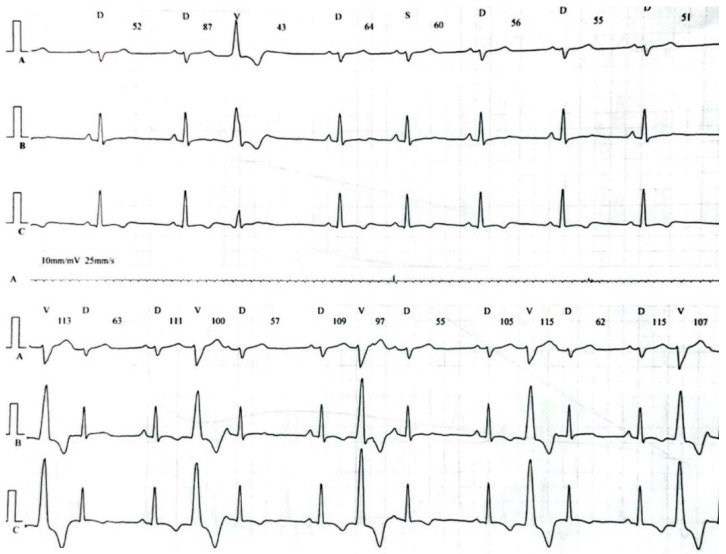

A 29-year-old male patient, a manual worker without history of overt infectious myocarditis, without classic risk factors for cardiovascular diseases, with mixed anxiety and depressive disorder, was treated with prescribed off-label medical marijuana (delta-9-tetrahydrocannabinol THC 19% and cannabidiol CBD < 1%, bred from Lemon Skunk Cannabis Strain in the form of unprocessed dried leaves) for around 3 years, smoked at least 3–4 times a day and was diagnosed with severe cannabis use disorder (continued use of cannabis despite clinically significant impairment) [ref. 6]. It was diagnosed by a psychiatrist according to the fifth version of the Diagnostic and Statistical Manual of Mental Disorders (DSM-5) with 8 out of 11 criteria met: hazardous use, social/interpersonal problems, neglected major roles, withdrawal, used larger amounts/longer, much time spent using, activities given up and craving [ref. 7]. Moreover, the patient was categorized as a chronic user [ref. 8]. He had been suffering from paroxysmal hemodynamically unstable ventricular tachycardia (VT). The first episode occurred 30 months ago and the patient was referred from an emergency room to a distant cardiology center, where upon coronarography, apart from myocardial bridge localized in the middle segment of the left anterior descending coronary artery no lesions in the coronary arteries were recorded. There were no specific abnormalities recognized in resting ECG (Figure 1, left panel). In the echocardiogram the structure and function of the heart was normal, apart from a mildly compromised left ventricular systolic function with left ventricular ejection fraction (LVEF) of 43%. At that time the patient did not consent to the proposed diagnostics of VT consisting of cardiovascular magnetic resonance imaging of the heart, electrophysiological study, genetic testing and therapy with subcutaneous implantable cardioverter-defibrillator. He received metoprolol in extended-release drug formulation (metoprolol succinate) of 25 mg q.d. due to intolerance of higher doses, potassium, magnesium and vitamin B6 supplementation. Within this period, the subject experienced at least six episodes of VT that required medical assistance. Moreover, 7 months earlier he was admitted to the catheterization unit again after an acute episode of retrosternal pain following marijuana intake. Once more, no lesions within the coronary arteries were observed in coronarography (Figure 2 and Figure 3). ECG showed no signs of ischemia, echocardiography was without segmental dysfunction of cardiac muscle, and LVEF equaled 40%. Noteworthy, the top troponin T serum concentration exceeded the upper end of the scale (>10,000 ng/mL), with CPK of 4167 U/L, CK-MB-428 U/L and CRP 3.4 mg/L. Non-ST-elevation myocardial infarction was diagnosed but the patient still declined extended diagnostics and marijuana addiction therapy. The treatment was supplemented with acetylsalicylic acid 75 mg q.d., clopidogrel 75 mg q.d., ramipril 1.25 mg q.d., rosuvastatin 10 mg q.d., eplerenone 25 mg q.d. and pantoprazole 20 mg q.d.

This time the individual was admitted to our cardiology center after another episode of VT, with cardiac arrest in the mechanism of VT at an emergency room (VT score—4 points, positive result of the Vereckei, Brugada and limb algorithms for the diagnosis of VT on ECG, Figure 4) treated with electrical cardioversion for further treatment [ref. 9,ref. 10]. The physical examination showed no significant abnormalities, the patient’s weight was 69 kg, height—190 cm, body mass index–BMI–19.11 kg/m2. Peripheral blood saturation—96%, body temperature—36.7 degrees C. Blood pressure was in the range of 100–110/60–70 mm Hg. In laboratory tests: white blood cells count—WBC—8.45 K/µL; hemoglobin—Hgb—13.3 g/dL; platelets count—PLT—260 K/µL; troponin T—317.6 ng/mL (norm < 30); N-terminal pro-brain natriuretic peptide—NT-proBNP—905 pg/mL; creatine phosphokinase—CPK—352 U/L; MB iso-enzyme of creatine kinase-CK-MB-24 U/L (6.8% CPK); thyroid-stimulating hormone—TSH—0.805 µU/mL; total cholesterol—2.6 mmol/L; low-density lipoprotein cholesterol—LDL—1.35 mmol/L; high-density lipoprotein cholesterol—HDL—0.89 mmol/L; triglycerydes—TG—0.87 mmol/L; glucose—5.6 mmol/L; creatinine—77 µmol/L (estimated glomerular filtration rate—eGFR > 90 mL/1.73 m2/min); sodium—141 mmol/L; potassium—3.61 mmol/L; chlorides—102 mmol/L; C-reactive protein—CRP—1.0 mg/L; d-dimer—413 ng/mL; alcohol—0.2 per mille; international normalized ratio- INR—1.23; activated partial thromboplastin time—aPTT—34 s; Abbott antigen test for SARS-CoV-2 virus negative; PCR test for COVID-19 also negative. The resting electrocardiogram revealed a sinus rhythm of 76 beats/min, the axis of the heart inclined moderately to the right, low voltage of QRS complexes in the limb leads, negative T waves in V5 and V6, and positive–negative in aVL. PQ equaled 160 ms, QRS—90 ms, QTc—440 ms (Figure 1, right panel). On echocardiography, the left ventricle was not enlarged (its end-diastolic dimension—55 mm), the interventricular septum was moderately thickened (11 mm in the diastolic phase), normal left ventricular systolic function was observed, with no segmental abnormalities of contractility (left ventricular ejection fraction—LVEF was 55%). No other significant abnormalities, including significant valve defects, were observed.

Fourteen days after discharge from the hospital, the patient reported for a follow-up visit. The wound healing after ICD implantation was normal, the parameters of the device (sensing, thresholds for atrial and ventricular stimulation, resistance of the pacing system and the high-energy system) were within the normal range. No complex ventricular arrhythmias were noted in the incorporated ICD ECG monitoring. Pharmacotherapy was maintained. After another 20 days, the patient was admitted to our cardiology center due to an electrical storm with recurrent VT in which some VT episodes were interrupted with antiarrhythmic therapy of the ICD, whereas some required adequate interventions of high-energy shocks. Temporary treatment with i.v. amiodarone and metoprolol tartrate p.o. was introduced and the patient was referred for urgent electrophysiological examination. The patient underwent RF ablation of the areas in the left ventricle within the interventricular septum responsible for the development and maintenance of tachycardia, resulting in the elimination of VT. Pharmacotherapy was maintained in the same way as after ICD implantation, including antiarrhythmic treatment with metoprolol sustained-release 50 mg/day. There was no recurrence of VT during the 3-month follow-up. In the 24-h control Holter ECG monitoring, 260 single ventricular accessory beats, without complex ventricular arrhythmias, were recorded (Figure 7). In addition, during each hospitalization, the patient was instructed about the harmfulness of the use of marijuana and alcohol, and after discharge from the ward he was referred to a mental health clinic to treat anxiety disorders and addiction to psychoactive substances.